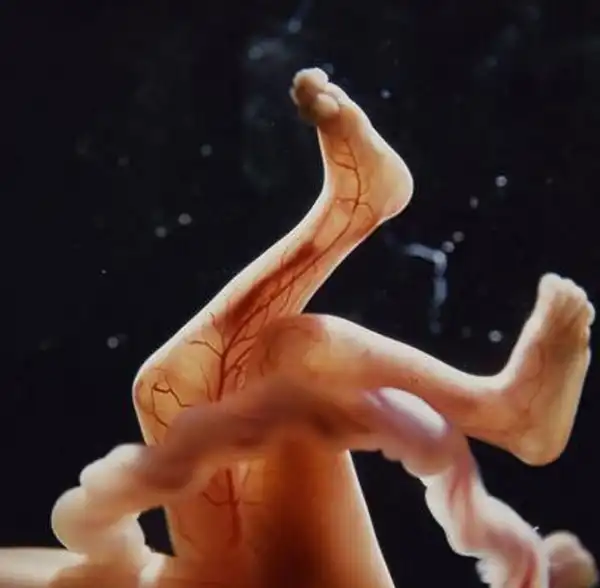

Сквозь тонкую кожу видна сеть кровеносных сосудов

16 недель